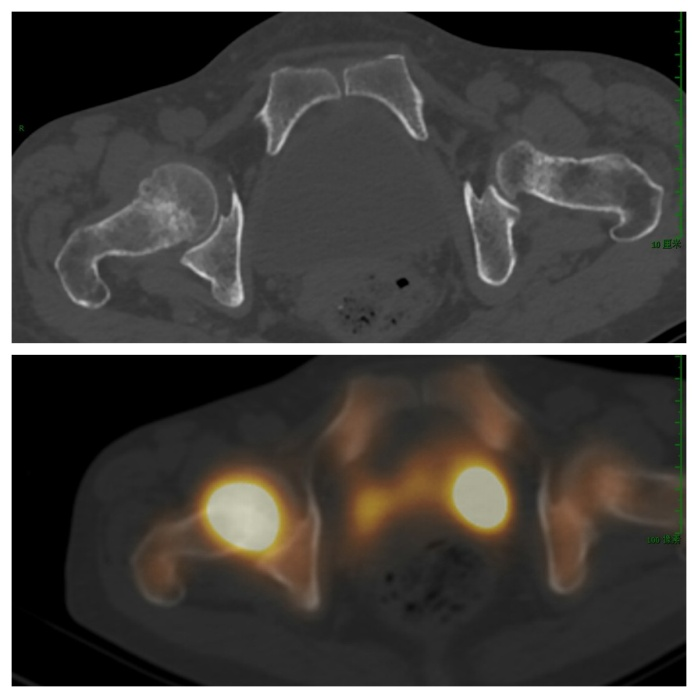

病例八:人工关节松动

右侧髋关节置换术后,疼痛明显,X线检查无异常。